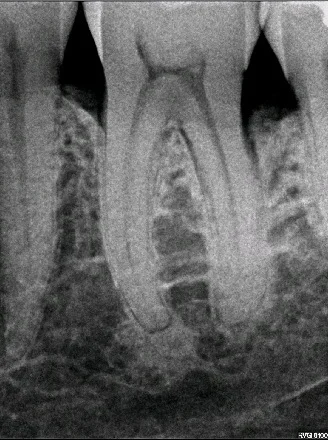

Before After

Great result of Perioscopy demonstrating before and after X-ray of the lower incisor. Initially this patient presented with a deep periodontal pocket, but only after one session of Perioscopy, a notable bony refill was evident on X-rays. Clinically his pockets reduced to 4 mm, and the patient was pleased to be able to save his tooth.